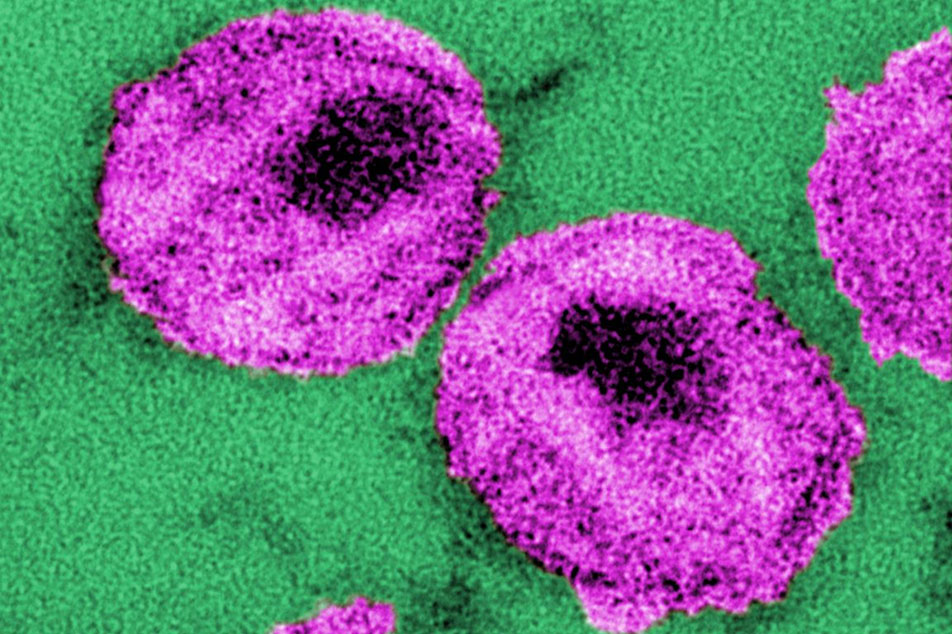

The fight to finally cure HIV

Immunology researcher Jerome Zack is a pioneer in developing innovative approaches aimed at eradicating HIV. With 40 million people worldwide still living with HIV and more than one million newly infected in 2024 alone, Zack believes stable funding is the key to turning scientific progress into a cure.

Giving children with immunodeficiency a chance to lead a normal life

For children with the rare condition ADA-SCID, day-to-day activities like going to school or playing with friends can lead to dangerous, life-threatening infections. If untreated, ADA-SCID can be fatal within the first two years of life. A blood stem cell gene therapy co-developed by UCLA’s Dr. Donald Kohn restored immune function in 59 of 62 children with ADA-SCID, with no serious complications reported.

Bruin brilliance: UCLA alumnus Frederick Ramsdell wins the Nobel Prize

When Fred Ramsdell lost cellphone reception during a hiking trip deep in the Rocky Mountains, he had no idea history was calling. Twelve hours later, he emerged from the wilderness to discover he’d won the 2025 Nobel Prize in physiology or medicine.

A ‘miracle’ drug for leukemia

In 1995, Melvin Mann, a major in the U.S. Army and the father of an 8-year-old daughter, was diagnosed with a rare and deadly blood cancer called chronic myelogenous leukemia. Unable to find a suitable bone marrow donor, he was told he had only a few years to live.

-